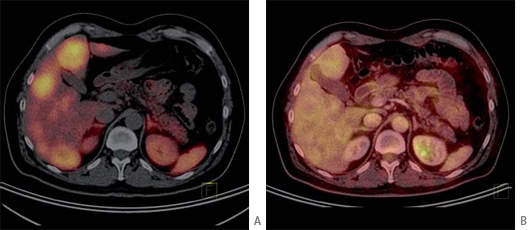

Tumores gastroenteropancreáticos

Este grupo (GEP) constituyen un grupo heterogéneo de tumores neuroendocrinos del estómago, páncreas e intestino. El más frecuente es el tumor carcinoide. El tratamiento primario es la cirugía aún en los pacientes con enfermedad metastásica, debido a que la resección parcial puede mejorar la calidad de vida, sobrevida y estado funcional. Las imágenes cumplen un papel importante para determinar la extensión de la enfermedad al inicio y en el seguimiento. Los estudios realizados con 111In pentatreotide muestran elevada sensibilidad para la detección de GEP a excepción del insulinoma. La sensibilidad para el gastrinoma metastásico, carcinoide y otros GEP son generalmente sobre 80% hasta 94%. La sensibilidad para la enfermedad metastásica tiende a ser superior a la de los tumores primarios (Figura 1) y en muchas ocasiones se encuentran lesiones no detectables por imágenes anatómicas. Utilizando Ga68 análogos de somatostatina se han obtenido excelentes resultados, con sensibilidades entre 82-100% (Figuras 2 y 3). El FDG tiene baja sensibilidad para la detección de estos tumores de lento crecimiento, bien diferenciados y bajo Ki-67, en cambio las imágenes con análogos de somatostatina presentan un patrón opuesto (Figura 4 y 5). Los tumores neuroendocrinos indiferenciados y agresivos presentan marcada avidez por la glucosa y pobre expresión de receptores de somatostatina y viceversa. Se ha visto que los pacientes con tumores con mayor expresión de Ki-67 evolucionan peor que aquellos con bajo Ki-6715. Los tumores neuroendocrinos que captan FDG tienen por lo tanto peor pronóstico16. En un estudio que comparó el rendimiento de cintigrafía con Octreoscan y FDG en pacientes con tumor carcinoide encontró que el 86% de los tumores primarios se localizaban con pentatreotide mientras que sólo el 57% con FDG. Pacientes con metástasis, el 69% fue positivo con el análogo de somatostatina, 47% con FDG y 56% con imágenes anatómicas17. Figuras similares se han obtenido con el uso de PET y Ga68análogos de somatostatina18,19.